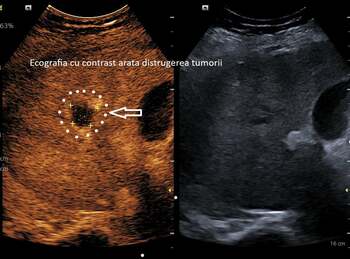

Spitalul Județean Craiova anunţă realizarea primei ablaţii cu microunde a unei tumori hepatice / La o lună după intervenţie s-a confirmat distrugerea completă a tumorii